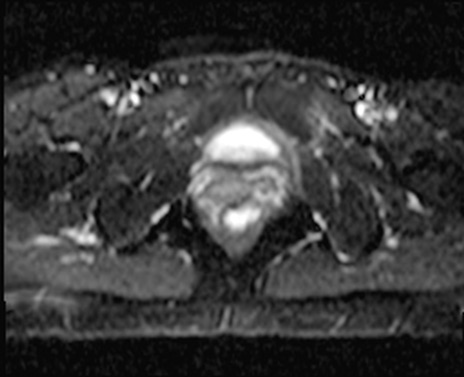

症例39 DWI/ADC

MRI(4日後)